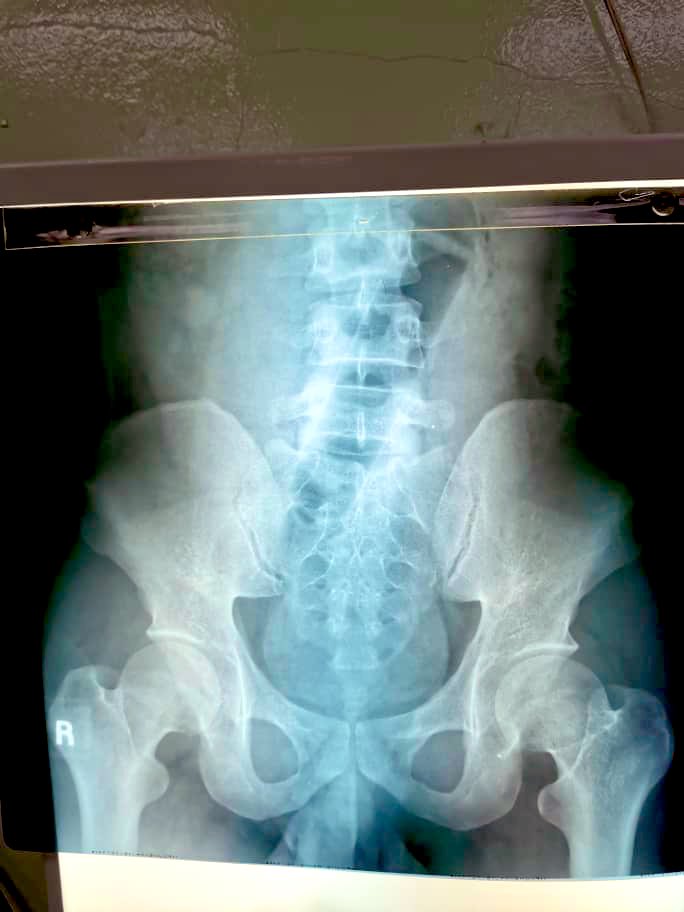

一名医生扎菲拉在推特分享到,她曾遇过一名病患,在凌晨4时许因为严重的腹痛,到急诊部求助,结果医生们经过检查后,发现他的肠穿孔导致肠道外胀气。

“很显然他是在玩气球气泵,或是脚踏车轮胎气泵,那是我见过‘最漂亮’的肠道外胀气,简直此生难忘,但我不会过于深入描述细节。”

Perforated bowel. Prettiest air under diaphragm I’ve ever since, sampai bila bila ingat https://t.co/6ZEGtfOR0c